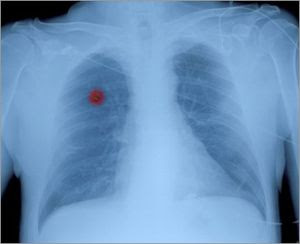

Immunothérapie Pour most cancers Du Poumon

Cancer du poumon commentguerir. Le cancer du poumon est l’un des cancers les plus fréquents. Près de 8 cas sur 10 se développent chez les personnes âgées de plus de 60 ans, habituellement des.

L’aliment préféré du most cancers santé corps esprit. Les cellules cancéreuses se nourrissent essentiellement deglucose (sucre). Voici les conseils pour se protéger du most cancers et éviter de le nourrir. Most cancers du poumon wikipédia. Historique. Le most cancers du poumon n'était pas fréquent avant l'arrivée de la cigarette ; il n'a même pas été identifié comme une maladie distincte jusqu'en 1761 [15. La révolution attendue contre le most cancers institut curie. Traiter le cancer en utilisant notre propre système de défense, le système immunitaire ce concept, c’est l’immunothérapie. File complet de l'institut curie. Cancer du poumon wikipédia. Les expressions most cancers du poumon et cancer bronchique désignent au sens strict une tumeur maligne du poumon, et par extension les carcinomes pulmonaires, qui. Pronostic et survie pour le most cancers du poumon société. Il est possible que les personnes atteintes d'un cancer du poumon non à petites cellules (cpnpc) se posent des questions sur leur pronostic et leur survie.